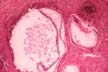

Among various amebas, the Entamoeba histolytica is the one that invades tissues in man. As long as it remains in the lumen of the colon (luminal phase), it causes no problems. When it invades the bowel wall (invasive phase) it causes a diarrhoic syndrome and may spread to the liver where it forms amebic abscesses which are usually solitary. The patient experiences pain and tenderness in that region and general symptoms with fever. The diagnosis of abscess is made with imaging techniques. The diagnosis of amebiasis is made by serological tests for amebic antibodies. The treatment is by drugs and rarely surgical. The first association of ameba with liver abscess was described by Loesch in St. Petersburg, Russia, in 1875.The figure shows clusters of ameba trophozoites in the tissue, large, up to 60 microns in diameter. This is the active mobile form. They have one small eccentric nucleus and cytoplasmic vacuoles sometimes containing red cells. The cystic form with round shape and multiple nuclei does not occur in the tissues.

Fig.147-Entamoeba histolytica

Clusters of trophozoites in the tissue, large, up to 60 microns in diameter. This is the active mobile form. They have one small eccentric nucleus and cytoplasmic vacuoles often containing red cell. The cystic form with spherical shape and multiple nuclei does not occur in the tissues.